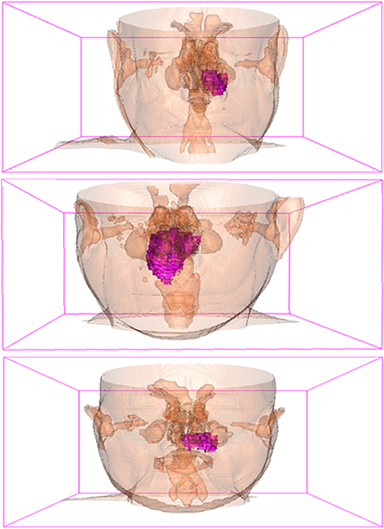

Comparison with ground truth. Some predicted results of MMFNet are shown in 2D images and 3D images in Figure 7 and Figure 8. As shown in these figures, although the shape and size of NPC are varied from each other, MMFNet can still accurately determine the regions of NPC and obtain the accurate contours of tumors. Through analyzing 2D images in figure 7, MMFNet has a capacity to fuse multi-modality MRI to reduce the confusion brought by intensity’ similarity between nearby tissues and NPC. The values of , and of MMFNet are shown in Table 1. MMFNet can reach the best results with , and .

Comparison with related works. Table 1 reports the values of , and for different methods. Predicted masks of different methods are illustrated in Figure 9 and Figure 10, which respectively present results in 2D and 3D images. Through comprehensively analyzing these results, the proposed MMFNet actually have the following properties:

(i) It directly fuses 3D MRI images rather than 2D slices. Thus, it can effectively use meaningful information from neighboring slices of MRI to realize NPC segmentation. As shown in Table 2, MMFNet can bring , and improvements in and compared to the best method based on 2D images (Multi-modality patch-based CNN). And Figure 10 shows that 3D-based methods have less isolated regions (false positives) than 2D-based ones.

(ii) It segments NPC by fusing multi-modality MRIs with the multi-encoder network. Thus, it can learn complementary and interdependent features from different modalities of MRI for final decisions. Additionally, comparing with input-level fusion networks and decision-level fusion networks, layer-level fusion networks (including MMFNet) can effectively capture informative features from different modalities of MRI and fuse low-level features and high-level features.

(iii) It uses a fusion block to fuse low-level features from different modalities of MRI and prepare these low-level features for the fusion with high-level features. Thus, it can more effectively fuse information from various sources. It also uses the self-transfer strategy to initialize the netwerk. Hereby, it can stimulate encoders to make full mining of meaningful features from modality-specific MRI. And it finally improve base multi-encoder-based network (Merging encoders’ fetures) by , and in and .